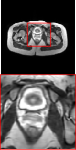

Clinical datasets. Clinical datasets include Brain (with T1 reference contrast and T2-FLAIR target contrast) and Pelvic (with T1 reference contrast and T2 target contrast). Specifically, the brain dataset consists of 637 slices from healthy subjects and 305 slices from tumor subjects. Among them, 512 slices of healthy subjects are utilized for training, 125 slices of healthy subjects are employed for validation and testing, and 305 slices of tumor subjects are used for additional testing. The pelvic dataset comprises 1600 slices, with a training, validation, and test split ratio of 7:1:2. The raw clinical datasets are generated by scanning with a 3T Philips Ingenia MRI Scanner. The scanning parameters for the brain are TE (T1): 2.3ms, TE (T2-FLAIR): 120ms. The scanning parameters for the pelvic are TE (T1): shortest, TE (T2): 130ms. The sum-of-squares (SOS) method is used for coil combination.

Figure 5 provides the qualitative comparison of the various methods on the four datasets at a scale of 4. The top, second, third, and bottom rows are the SR results under the FastMRI, clinical brain, clinical tumor and clinical pelvic datasets, respectively. The red boxes indicate the zoom-in region of complicated anatomical structures along with their corresponding error maps. Note that the brighter textures in the error maps, the lower the quality of the reconstructed images. As can be seen, compared to methods based on Transformers and CNNs, diffusion-based methods like DisC-Diff and DiffMSR (Ours) are capable of reconstructing high-realistic images with promising reconstruction metric scores (PSNR and SSIM). Nevertheless, while DisC-Diff can reconstruct high-precision MR images, it does not preserve the structure present in the original HR images, introducing some additional information that can affect medical diagnosis. In contrast, our method combines DM and PLWformer, which can preserve the original image’s structure while restoring high-frequency information.